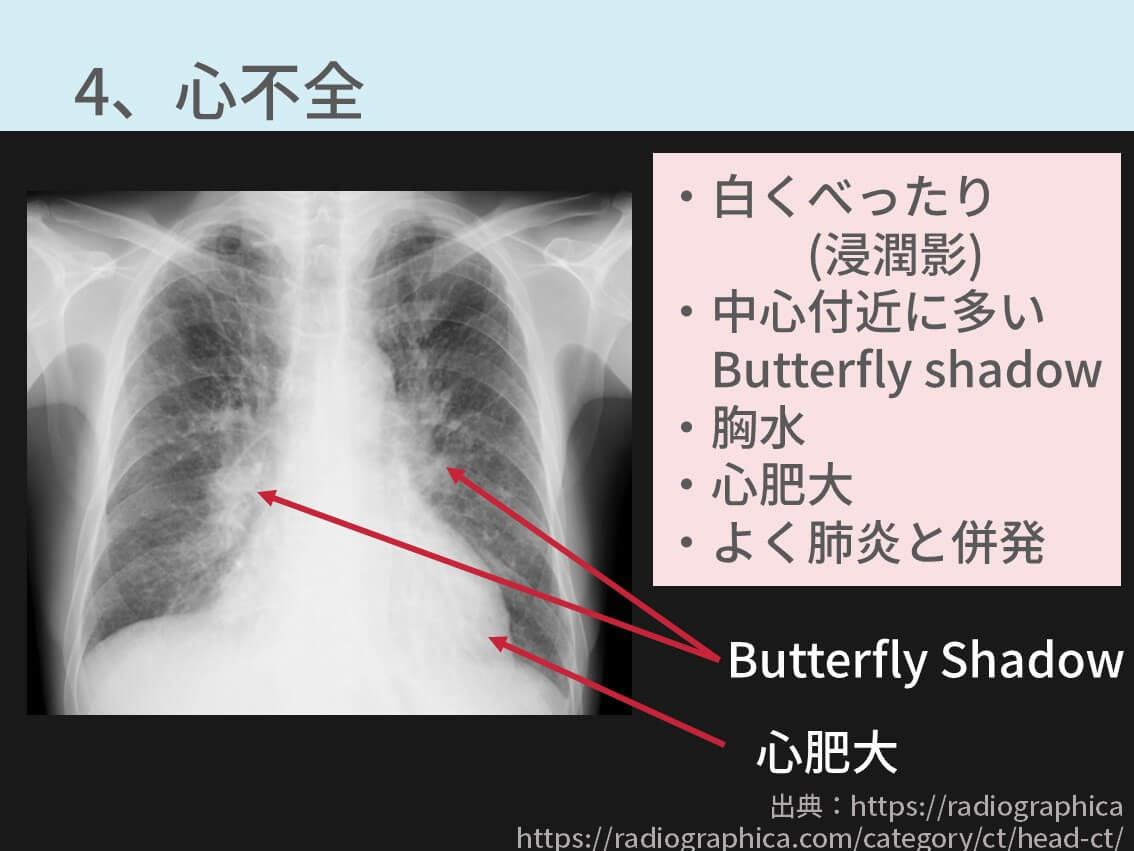

解答・解説】胸部異常陰影にて紹介受診した40 歳代女性|実践!画像診断Q&A|羊土社:レジデントノート - 羊土社, 胸部レントゲンの異常所見まとめ【保存版】※重要な疾患7つを解説 | コキュトレ,

胸部レントゲンの異常所見まとめ【保存版】※重要な疾患7つを解説 | コキュトレ, 胸部異常陰影 | 浅草橋駅前総合クリニック